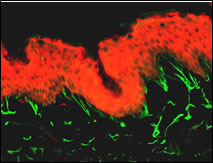

Abb. 4: Immunfluoreszenz-Darstellung der Elastine in normaler menschlicher Haut und im Ganzhautmodell

Elastin in normaler menschlicher Haut (oben) und im Hautequivalent (unten, 250fache Vergößerung). Immunfluoreszenzstudie an gefrorenen Hautschnitten nach 14 Tagen Kultivierung an Air-Liquid Interface.

In dem hier verwendeten Hautmodell exprimieren die Fibroblasten auch Elastin (Abb. 4). Der Einfluss verschiedener Wirkstoffe auf Elastinmenge und Ausrichtung der Elastinfasern ist Gegenstand der aktuellen Forschung.